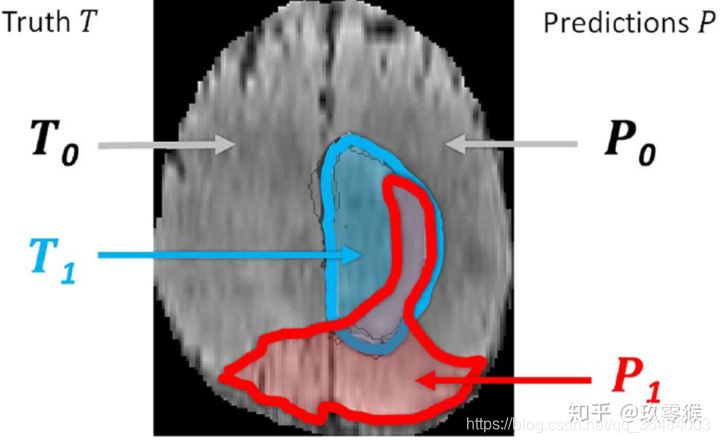

1、What is T 1 、 T 0 、 P 1 、 P 0 T_1、T_0、P_1、P_0 T1、T0、P1、P0? 1

T1蓝色部分表示真实脑肿瘤区域(GroundTruth)

T0蓝色的其它部分为正常脑区域

P1红色部分表示预测的脑肿瘤区域

P0 红色的其它部分为预测的正常脑区域

(a) TP:True Positive,被判定为正样本,事实上也是正样本 ,即蓝色与红色的交集

(b) TN:True Negative,被判定为负样本,事实上也是负样本,即红色与蓝色以外区域

(b) FP:False Positive,被判定为正样本,但事实上是负样本,即红色中除了蓝色部分

(d) FN:False Negative,被判定为负样本,但事实上是正样本,即蓝色中除了红色部分